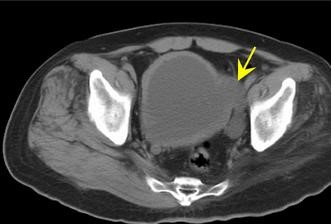

控制排尿功能的中枢神经系统或周围神经受到损害而引起的膀胱尿道功能障碍称为神经原性膀胱。

尿不畅或尿潴留是其最常见的症状之一,由此诱发的泌尿系并发症,如上尿路损害及肾衰竭等是患者死亡的主要原因,神经源性膀胱通常是其它病情引发的后遗症,病因有多种例如脊髓损伤、先天性脊柱裂、脊髓肿瘤、脊髓囊肿、椎管狭窄等;其他一些医源性原因,例如盆腔手术、子宫全切术、前列腺癌引起的神经源性膀胱。

尿路感染是神经源性膀胱最常见的并发症,10%~15%的患者可发生尿路结石,膀胱输尿管返流在神经源性膀胱中发生率为10%~40%,通常为可逆性,当排尿情况改善,剩余尿减少,膀胱压力减低时有自行好转的可能,还可并发肾盂肾炎,肾衰竭,肾积水等,病人饱受折磨。